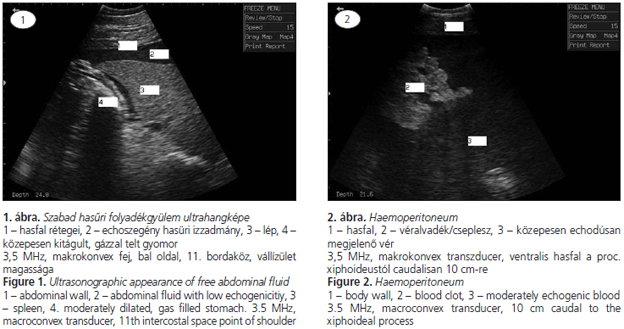

A vizsgálatot szisztematikusan (caudocranialisan és dorsoventralisan) célszerű elvégezni. A transabdominalisan elvégzett vizsgálat során azonosítható a szabad hasűri folyadék megléte, helye, kiterjedése. A folyadék jellegére (transsudatum, vér, vizelet, szeptikus izzadmány), annak echogenitása alapján, szintén következtethetünk (1., 2., 3. és 4. ábra). A vizsgálat során azonosíthatóak a fibrinlerakódások, a tályogok, az adhéziók, az ileusos bélszakaszok is (2, 3). Hascsapolás és drén behelyezése során megkereshető a ventralis hasfal azon pontja, ahol a legmagasabb a folyadékoszlop.

A kétdimenziós B-mód ultrahangvizsgálat kiválóan alkalmas vizsgálati módszer a betegség diagnosztizálására, valamint ultrahangárnyékban elvégzett hascsapolásra vagy drén behelyezésére. A vizsgálathoz az állatot nem feltétlenül szükséges borotválni, amennyiben a szőr megfelelően rövid. A jobb kontaktus érdekében izopropil-alkohol vagy metilcellulóz gél használható. A vizsgálatot lineáris, makro- és mikrokonvex transzducerrel is végezhetjük. Felnőtt ló esetében 2–4, csikóknál 3,5–5 MHz az ideális frekvencia, ami 15–35 cm mélységű szöveti penetrációt tesz lehetővé.